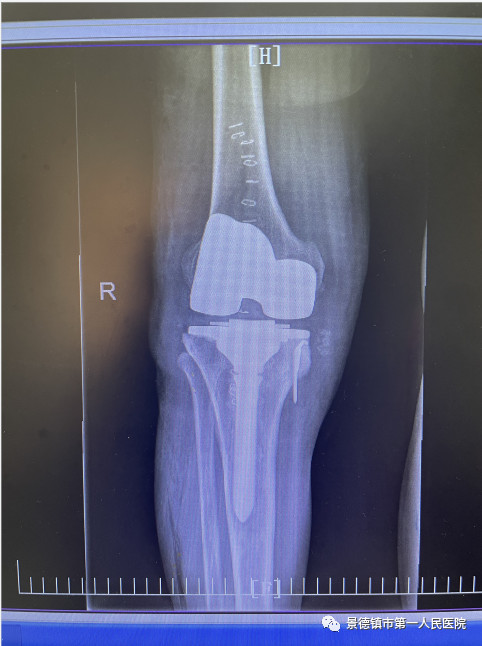

经过多次术前讨论,袁志峰与手术团队医师刘会文共同讨论出手术方案。行表面膝关节置换术,尽量的保留患者更多的骨量,为20年甚至30年以后面临的再次置换提供一个充足的骨量储备。并利用目前医疗领域新的3D数字打印技术,精准进行截骨和假体安放,有效避免术后患者双侧因软组织不平衡而造成的力线偏移,假体就更加稳定,使用的寿命更加长。

8月23日,是程小华“重获新生”的日子,1个半小时的手术过程,在程小华家人心中像过了一个世纪那么长。当得知手术非常成功后,他的家人心中如同放下一块大石。这段时期,骨二科的医护人员经常在程小华的病房指导他复健,9月17日出院时,程小华已经可以像正常人一般行走,他仍然需要积极进行康复锻炼,逐步恢复腿部肌肉。